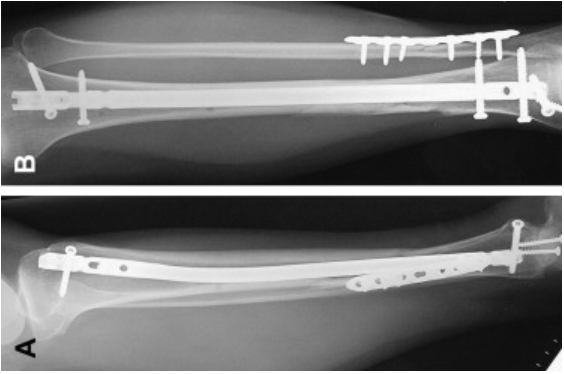

Following the treatment that occurs right after the injury, there must be surgery, particularly by utilizing metal rods (intramedullary rods), plates, and screws, or external fixation.

Intramedullary rods are inserted into the follow end of a long bone and then run through the middle of the bone with screws to secure it at the top and bottom. It functions to keep the bone stabilized and aligned.

X-ray image of intramedullary rods

Plates and screws are a technique where they are attached to the outside of the bone to hold broken pieces together.

External fixation is when the bone is stabilized by using a frame outside the body. This is used for severe compound fractures and is only temporary until a permanent fix, such as a rod or plate, can be done.